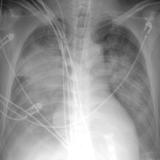

APE 6

+ IABP

Date: 01/13/2008

Views: 3390